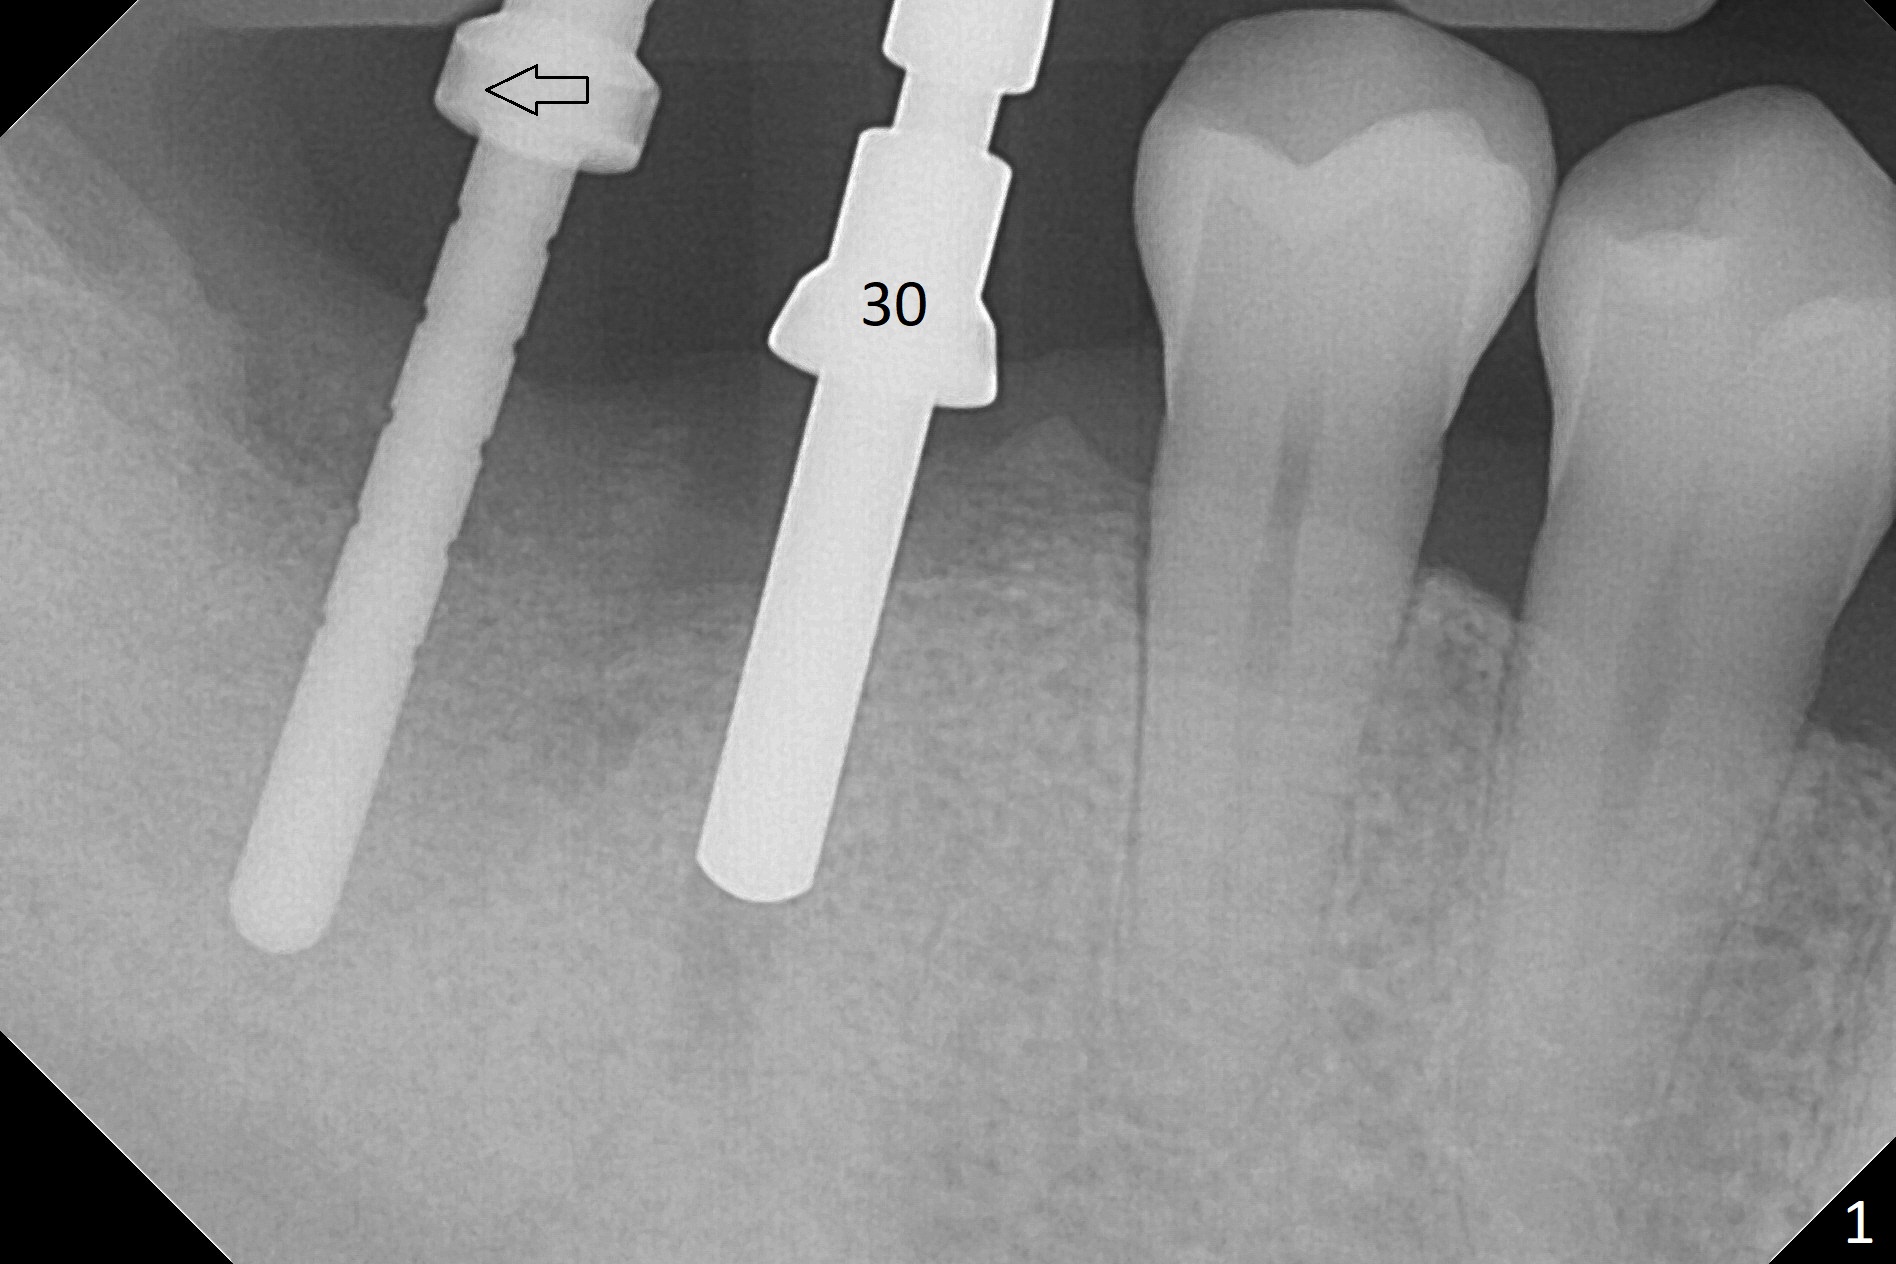

Osteotomy at the sites of #30 and 31 is initiated with Magic Split, followed by Magic Expanders (3.0 and 3.8 mm) at #31. Initial depth of osteotomy is 13 mm with 2.2 mm drill (Fig.1). After adjustment of the trajectory at #31 (Fig.1 arrow) and deepening the osteotomy by 2 mm, dummy implants are placed with stability (Fig.2). Following increase in osteotomy at #31, the larger implant in fact loses stability (Fig.3). The loose implant is pushed distal (Fig.4 arrow) with placement of autogenous bone mesial (*). The stable implant at #30 (Fig.3) and its abutment (Fig.4) are used as a post to hold periodontal dressing, which covers the wound at #31 after placement of collagen plug and suturing. In fact the same technique could be used when socket preservation was performed if an implant were placed at #30 at the same time. When the periodontal dressing dislodges, the wound at #31 heals uneventfully (Fig.5,6). The bone graft seems to remain in place 3 months postop (Fig.7). The implant is uncovered with placement of a 6.8x7 mm healing abutment 4 months postop. When a cementation abutment is placed and prepped, the buccal margin is much lower than the lingual (Fig.8 taken prior to cementation). The patient enjoys mastication with the new implant crowns 3.5 months post cementation (Fig.9).